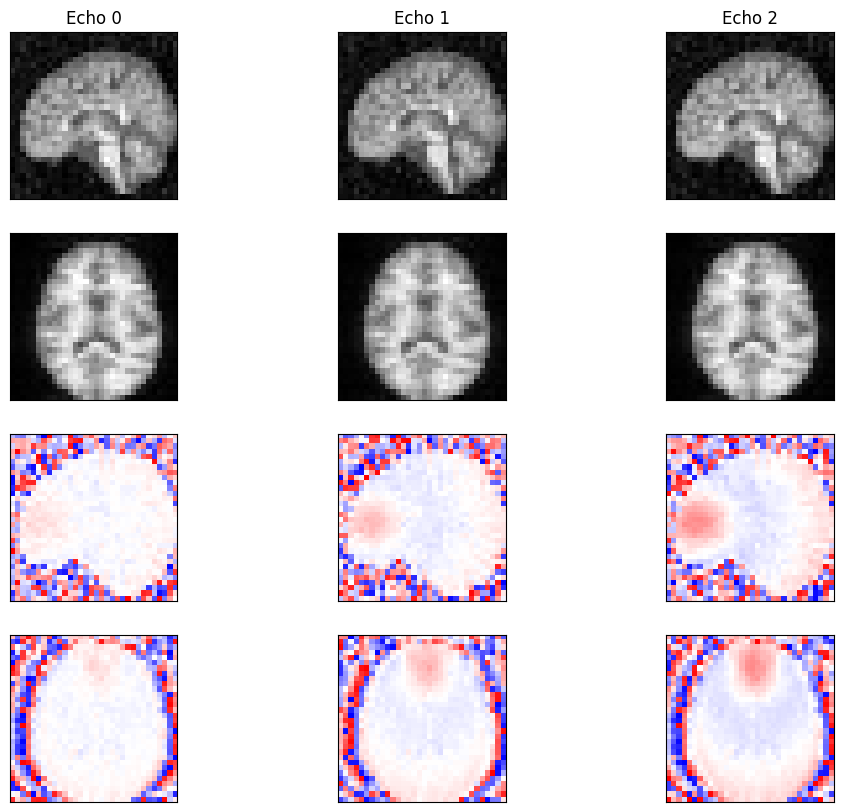

Reconstruction#

Reconstruct the 3D image from the k-space data using direct reconstruction.

fig, ax = plt.subplots(4, 3, figsize=(12, 10))

for cax in ax.flatten():

cax.set_xticks([])

cax.set_yticks([])

idat = idata.data.numpy().squeeze()

z_mid, x_mid = idat.shape[-3] // 2, idat.shape[-1] // 2

for echo in range(idat.shape[0]):

ax[0, echo].imshow(np.abs(idat[echo, :, :, x_mid]), cmap='gray')

ax[1, echo].imshow(np.abs(idat[echo, z_mid, :, :]), cmap='gray')

ax[2, echo].imshow(np.angle(idat[echo, :, :, x_mid]), cmap='bwr', vmin=-np.pi, vmax=np.pi)

ax[3, echo].imshow(np.angle(idat[echo, z_mid, :, :]), cmap='bwr', vmin=-np.pi, vmax=np.pi)

ax[0, echo].set_title(f'Echo {echo}')

_images/771968b25f6b880ef1c4efb83c57bfa590d72f42f4d604768f31184d06d4689c.png